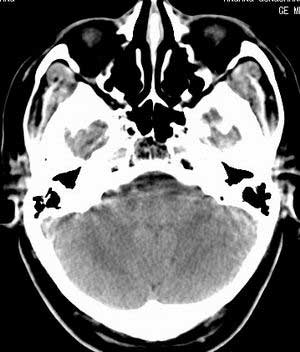

患者男,58岁。耳爆震伤后耳聋2年余,而后双耳道肿胀,间断性流脓。近一月来头痛、恶心、呕吐,右眼红痛,不能入眠。

在平扫时,见右侧枕骨下方小脑半球表面带状模糊稍高密度影,考虑为耳源性脑内感染。

平扫右侧岩骨与枕骨交角内侧脑质内见淡片状密度增高影,内缘清晰。增强图象上未见明显显示。

考虑:1)伪影可能,建议复查头ct平扫。

2)加照头ct骨窗,以显示乳突气房内是否有病变。